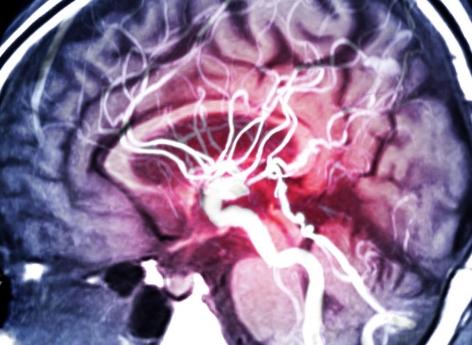

Le Pr Mickaël Mazighi, neurologue à l'Hôpital Lariboisière, à Paris, et chercheur INSERM, expliques les risque hémorragique associé à l'HTA souvent observée à la phase aiguë d'un AVC ischémique et décrypte la première étude randomisée sur la baisse de la pression artérielle